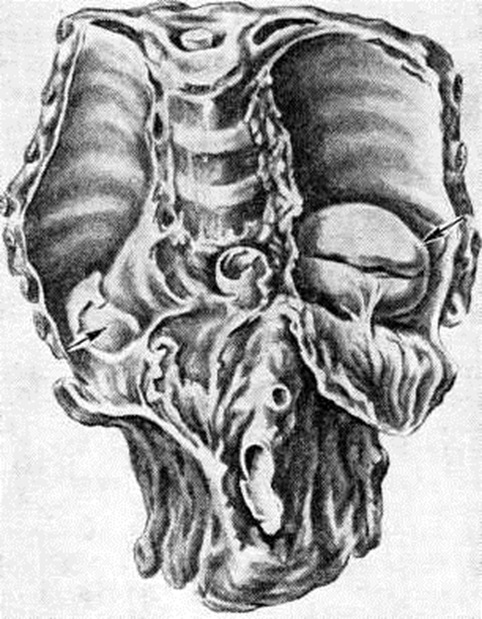

Возможны различные пути распространения туберкулёзного процесса из первичного очага через переднюю, заднюю и боковую поверхности тела позвонка (внедисковый путь), а также через межпозвоночный диск (внутридисковый путь). Процесс, распространяющийся внедисковым путем, приводит к обширным разрушениям позвонков. Прорываясь через переднюю поверхность тела позвонка, гной отслаивает переднюю продольную связку, распространяется под ней, образуя превертебральный абсцесс (рисунок 1, а), и вызывает контактное поражение других позвонков, так называемый поверхностную костоеду. Превертебральные абсцессы в зависимости от направления распространения гноя вызывают восходящий или нисходящий периостит (смотри полный свод знаний). При прорыве очага под заднюю продольную связку обычно возникают неврологический нарушения, обусловленные отёком спинного мозга (смотри полный свод знаний), сдавлением его гноем (рисунок 1, б), секвестрами, выступающими кзади остатками разрушенных позвонков, так называемый клином Урбана, утолщением мозговых оболочек вследствие пахименингита (смотри полный свод знаний). Характер неврологический нарушений определяется локализацией процесса и механизмом сдавления спинного мозга. При прорыве гноя через боковые поверхности тела позвонка образуются паравертебральные абсцессы, которые распространяются преимущественно в стороны от позвоночника и потому в меньшей степени контактно поражают тела соседних позвонков. В грудном отделе позвоночника такие абсцессы могут принимать форму веретена, полушарий, чечевицы, шаров, или так называемый ласточкиных гнезд (рисунок 2). В нижележащих отделах — нижнем грудном, поясничном и пояснично-крестцовом — абсцессы распространяются по мышцам, прикрепляющимся к пораженным позвонкам. Так, из поясничного отдела гной может распространяться в подвздошную область и далее — через мышечную лакуну на бедро. Из пояснично-крестцового отдела наиболее типичный путь распространения по ходу грушевидных мышц в ягодичную область. При внутридисковом пути процесс распространяется вертикально в направлении межпозвоночного диска, затем вовлекается студенистое ядро, а через него контактно — соседний позвонок (рисунок 1, в). Внутридисковое распространение гноя в большинстве случаев сочетается с малой деструкцией позвонков и наклонностью к отграничению процесса.

Деструкция тел позвонков сопровождается их клиновидной деформацией — это ведёт к углообразному кифотическому искривлению позвоночника (смотри полный свод знаний: Кифоз) в виде горба (gibbus), что является самым характерным признаком Спондилит У детей кифоз появляется раньше и прогрессирует быстрее, чем у взрослых. Наибольшей степени кифотическая деформация достигает при локализации процесса в грудном отделе позвоночника. С появлением кифоза постепенно деформируется вся грудная клетка, смещаются и сдавливаются находящиеся в ней сосуды и органы, развивается легочно-сердечная недостаточность и другие нарушения. При боковой деструкции тел позвонков развивается сколиотическая деформация (смотри полный свод знаний: Сколиоз), более характерная для поясничного отдела позвоночника (рисунок 3). Чаще имеют место сочетанные деформации. Межпозвоночные диски вследствие нарушения трофики постепенно уменьшаются в размерах и истончаются. Тела позвонков, разрушаясь, сближаются, соприкасаются и при длительно существующем процессе образуют нередко единый конгломерат, блок тел позвонков, включающий очаги деструкции, остатки разволокнённых дисков. Задние отделы позвоночника также сливаются воедино в виде панциря, закрывающего спинной мозг.